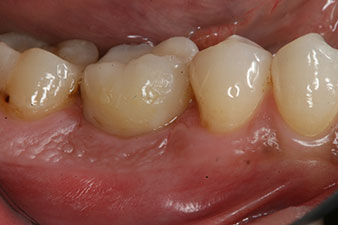

Kompositkrone

Abb. 9: Die definitive Kompositkrone wurde im Labor auf ein PEEK-Hybrid-Abutment geklebt und kann sofort verschraubt werden.

Die Abschlussbilder zeigen die verschraubte monolithische Kompositkrone in situ und die Röntgenkontrolle (Abb. 9 und 10) (6).